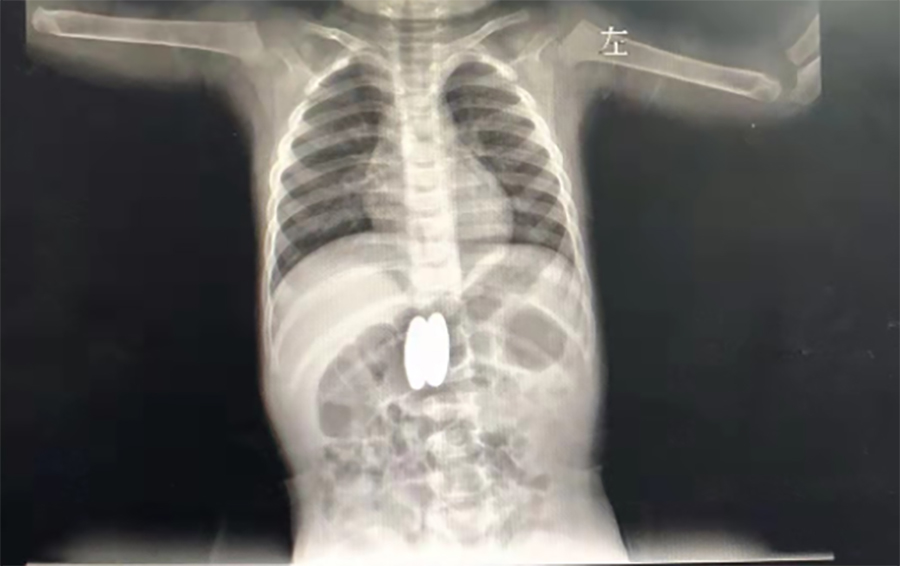

正月初八,2岁的壮壮(化名)感冒加重了,不断咳嗽,家人带他到当地医院就诊。在拍肺CT时,医生发现他的胃、肠里竟然有两个异物,而且两处异物竟吸在一起了。

▲当地医院CT

吞俩磁力球,很可能穿孔

家长回想起春节前大宝的4个磁力球少了2个,怎么找都没找到,看来是被二宝误吞了。当地医生担心壮壮胃肠穿孔,建议他们马上带壮壮到啪啪网 就诊。在内镜中心,副主任边鹏经内镜检查,发现壮壮吞下的磁力球直径有2cm,呈椭圆形,分别在胃体后壁、十二指肠球部。考虑到误吞异物时间较长,两球相吸处很可能已经穿孔,内镜中心同外科会诊,迅速研究解决方案。边鹏说,一是手术治疗,但十二指肠周围有胆管、大血管等,周围组织特别敏感,一旦出问题,危险性极大;二是保守治疗,在生命体征平稳的情况下,暂时观察,待胃、肠穿孔形成窦道,就可以不用手术,在内镜下把异物取出来了。经沟通,家长选择保守治疗,择日再来取出异物。